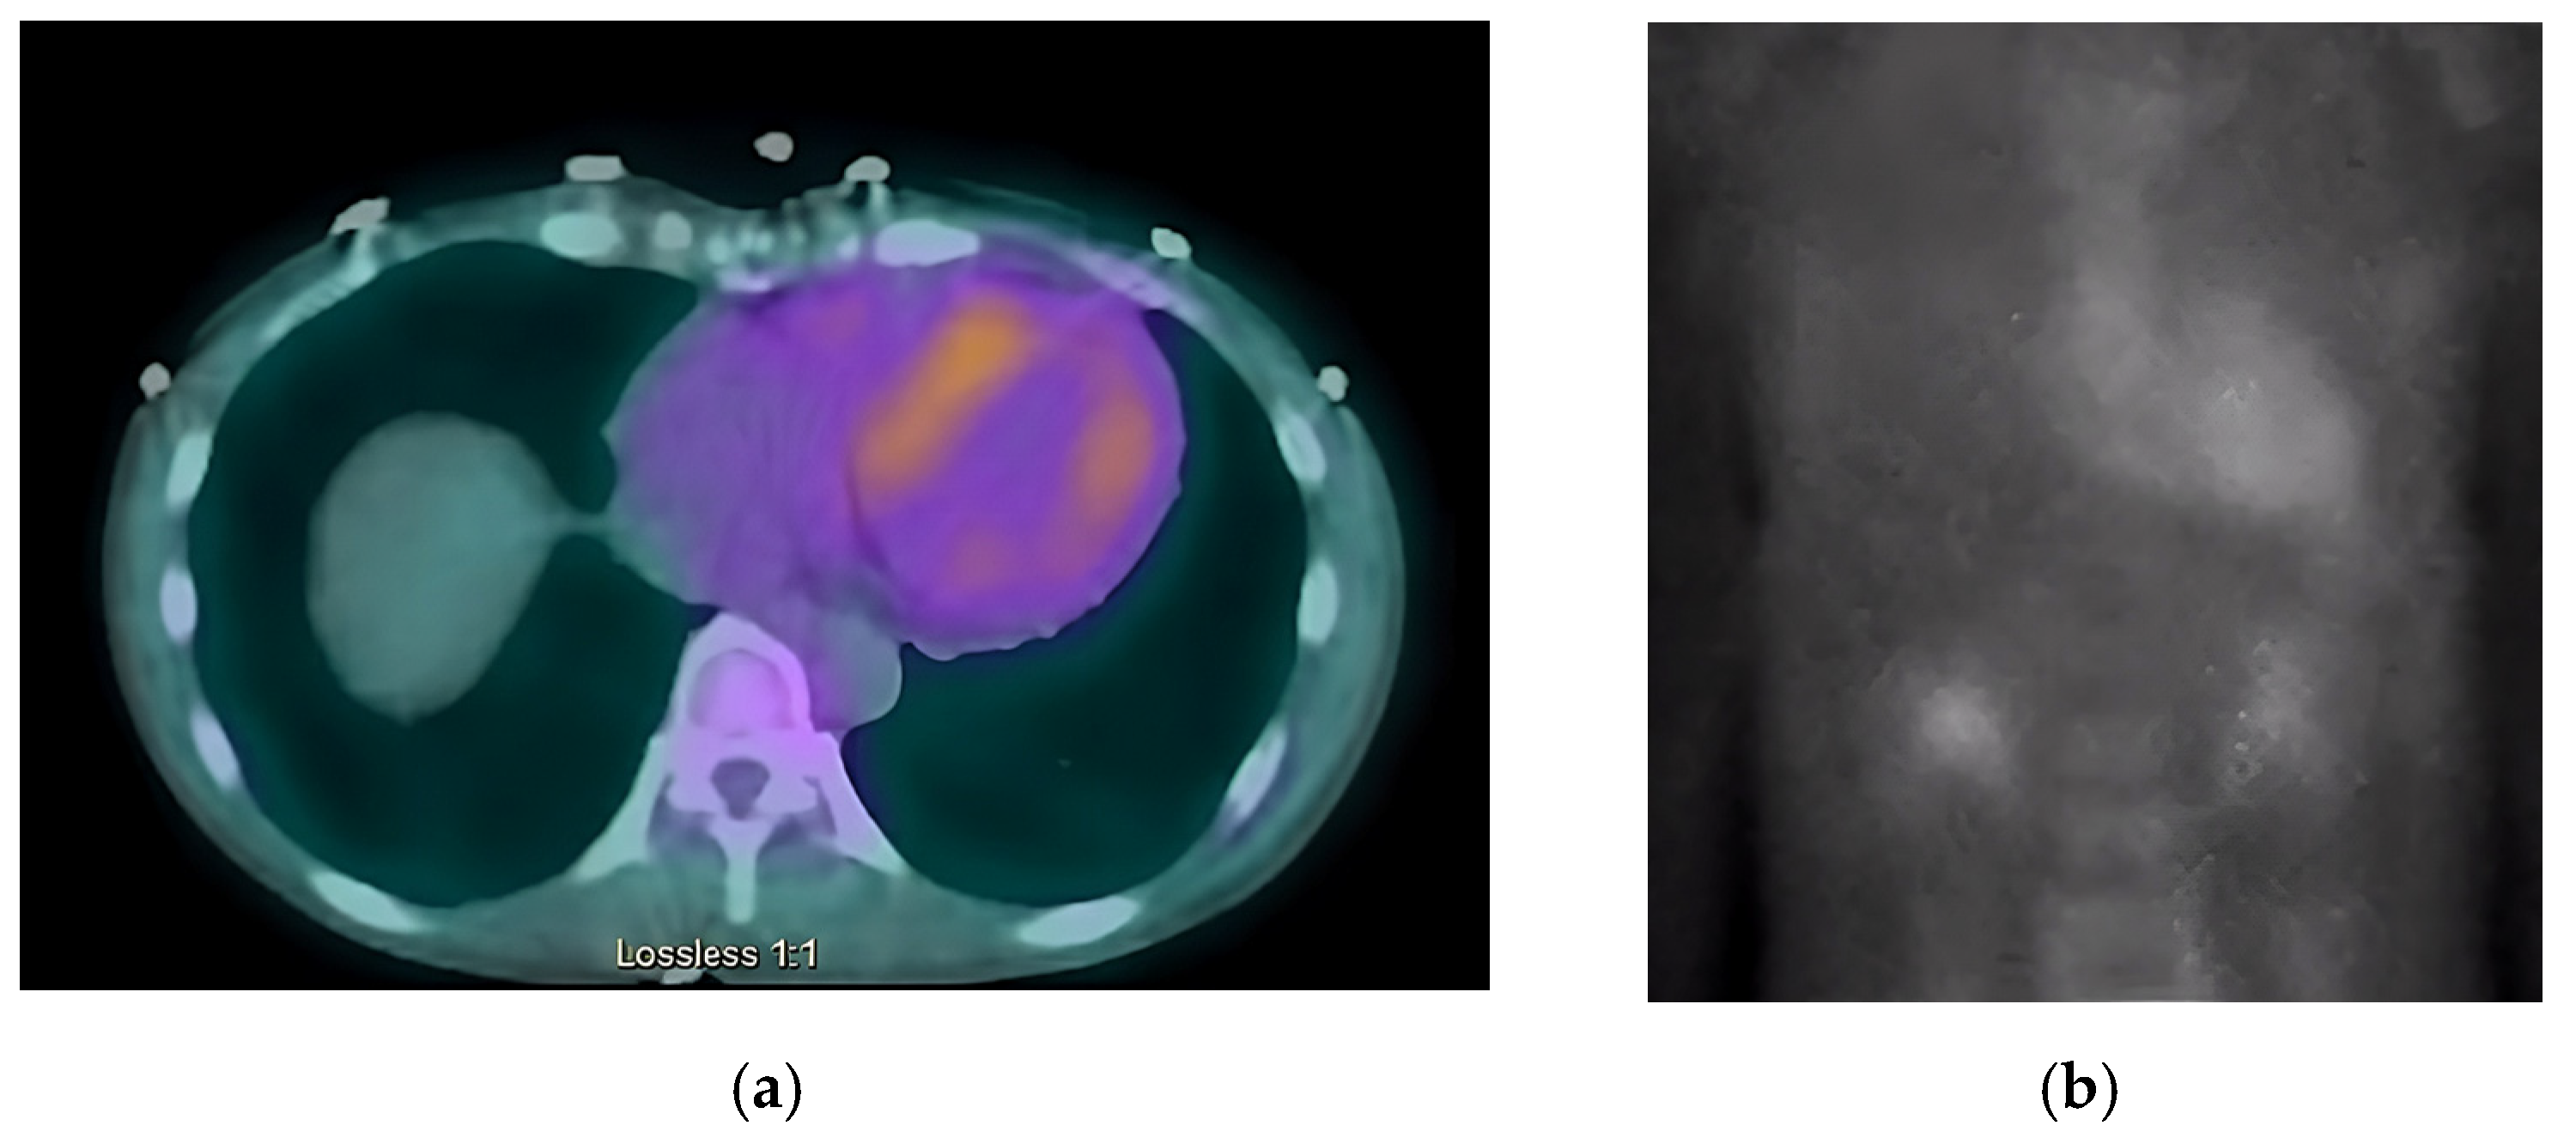

The chest radiograph did not show any acute findings. Electrocardiogram (ECG) (Figure 1) showed normal sinus rhythm with first-degree atrioventricular block, left axis deviation, and low voltage in limb leads. No prior echocardiogram (ECHO) was available, so an initial ECHO was obtained showing preserved ventricular ejection fraction (EF), moderate left ventricular hypertrophy (LVH), stage II diastolic dysfunction, and small pericardial effusion (Figure 2 and Figure 3).

Figure 4. SPECT in an ATTR cardiac amyloidosis patient. Evidence of uptake of 99mTc-PYP in the myocardium. (a) Quantitative SPECT/CT; (b) Semiquantitative analysis of 99mTc-PYP myocardial uptake.